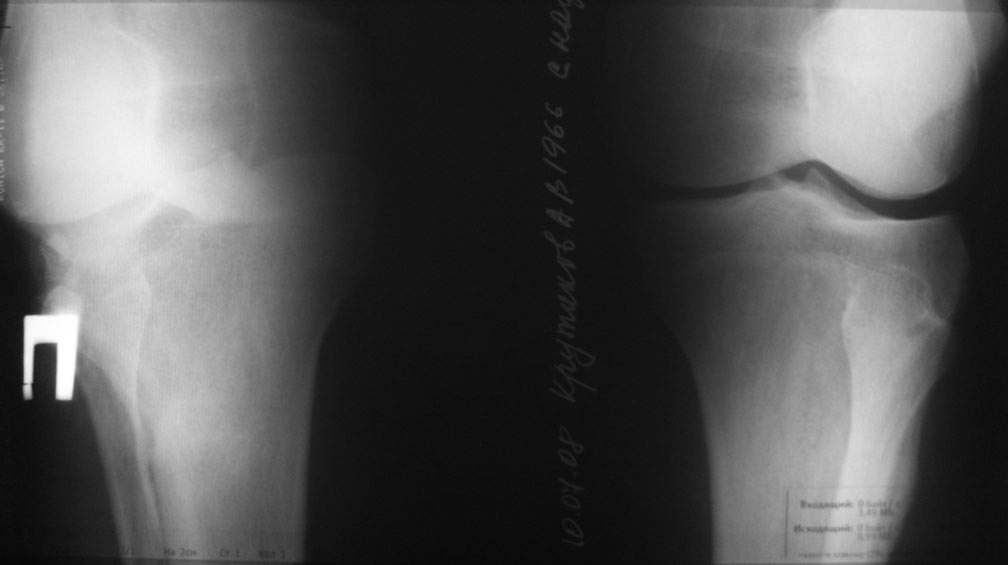

пациент наконец то объявился вновь и мы смогли выполнить новые снимки как лежа так и в нагрузке

Имя     : nagruzka.jpg

Тип     : image/jpeg

Размер  : 30147 байтов

Описание: отсутствует

Url     : http://weborto.net:8080/pipermail/ortho/attachments/20080714/b21730ce/attachment-0004.jpg